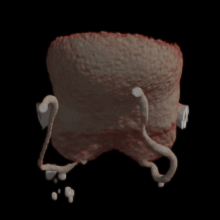

Пацієнтка 53 роки.

В анамнезі — екстирпація матки (12.2024) з приводу міоми.

• за результатами дообстеження — утворення запального характеру в порожнині таза із залученням додатків

Тубооваріальне утворення додатків матки.

Відмежований хронічний тазовий перитоніт.

Лапароскопія. Видалення запального тубооваріального утворення додатків матки в умовах відмежованого хронічного тазового перитоніту. Санація черевної порожнини.